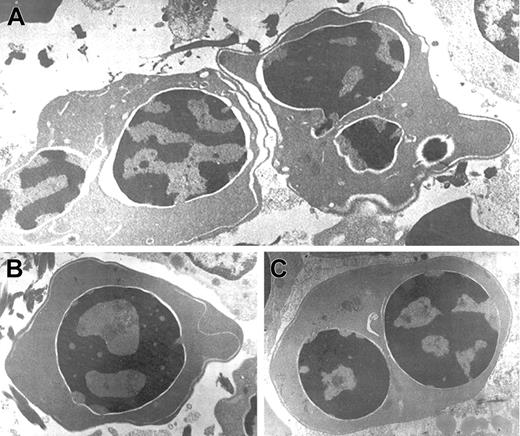

In this period, an extensive study ruled out red cell enzyme, membrane, hemoglobin, and thalassemic diseases. Tests for maternofetal isoimmunization were normal, and a bone marrow biopsy showed a normal osteogenesis with erythroid hyperplasia, excluding an aplastic red cell anemia. His red cells showed a normal agglutinability with anti-i antibody, and an acidified serum lysis test was negative (HEMPAS negative) in 3 samples and against 25 sera. At 3 months of life when the immunohematologic study was carried out, his hemoglobin was 67 g/L, mean corpuscular volume was 80 fL, platelets were 568 × 109/L, leucocytes were 10.2 × 109/L, including 10% of nucleated red cells, and reticulocytes were 0.5% (0.013 × 1012/L). Red cell morphology in peripheral blood showed scant binuclear erythroblasts (2%) (Figure 1).

Optical microscopy morphology of peripheral and bone marrow hematopoiesis.

Binucleate erythroblast in peripheral blood (A). Erythroid hyperplasia with marked abnormalities (binucleate, trinucleate, and multinucleate late erythroblasts) (B,C,D). Abnormal erythroblasts showing anomalous distribution of chromatin (C,D), binucleate erythroblasts, and isolated trinuclear, tetranuclear (B), and aberrant multinuclear erythroblasts (B,D). May-Grünwald-Giemsa stain. Original magnifications: A and D, × 400; B, × 200; C, × 1000.

At the age of 2 months a bone marrow examination showed erythroid hyperplasia and markedly abnormal erythropoiesis (Figure 1), including a substantial proportion of binuclear erythroblasts (20%) and a much smaller proportion of trinuclear, tetranuclear, and multinuclear erythroblasts (2%). Sideroblastic or megaloblastic anemias were ruled out. Granulocytopoiesis and megakariocytopoiesis were normal.